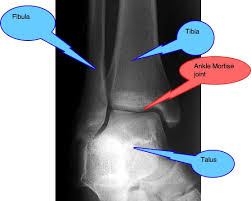

Mortise ankle structures best demonstrated

Ankle mortise joint space open between medial and lateral malleoli.

Minimal superimposition at the distal tibiofibular joint.

The mortise joint refers to the space formed by

• Medial malleolus

• Lateral malleolus

• Talus between them.